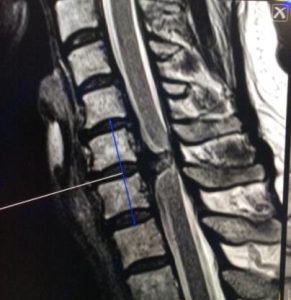

Prueba de elección para tumores de columna y médula espinal. Evalúa partes blandas, relación con la médula y raíces, y detecta compresión, edema, necrosis o hemorragia intratumoral.